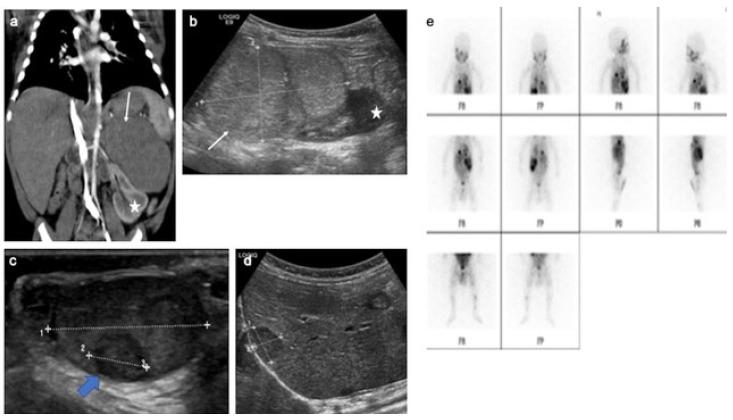

Pre- and post-pubertal testicular tumors are two distinct entities in terms of epidemiology, diagnosis and treatment. Most pre-pubertal tumors are benign; the most frequent are teratomas, and the most common malignant tumors are yolk-sac tumors. Post-pubertal tumors are similar to those found in adults and are more likely to be malignant. Imaging plays a pivotal role in the diagnosis, staging and follow-up. The appearance on ultrasonography (US) is especially helpful to differentiate benign lesions that could be candidates for testis-sparing surgery from malignant ones that require radical orchidectomy. Some specific imaging patterns are described for benign lesions: epidermoid cysts, mature cystic teratomas and Leydig-cell tumors. Benign tumors tend to be well-circumscribed, with decreased Doppler flow on US, but malignancy should be suspected when US shows an inhomogeneous, not-well-described lesion with internal blood flow. Imaging features should always be interpreted in combination with clinical and biological data including serum levels of tumor markers and even intra-operative frozen sections in case of conservative surgery to raise any concerns of malignity. This review provides an overview of imaging features of the most frequent testicular and para-testicular tumor types in children and the value of imaging in disease staging and monitoring children with testicular tumors or risk factors for testicular tumors.

青春期前和青春期后的睾丸肿瘤在流行病学、诊断和治疗方面是两种不同的疾病实体。大多数青春期前肿瘤是良性的;最常见的是畸胎瘤,最常见的恶性肿瘤是卵黄囊瘤。青春期后肿瘤与成人的肿瘤相似,更有可能是恶性的。影像学在诊断、分期和随访中起着关键作用。超声检查(US)的表现对于区分可进行保留睾丸手术的良性病变和需要根治性睾丸切除术的恶性病变特别有帮助。文中描述了一些良性病变的特定影像学表现:表皮样囊肿、成熟囊性畸胎瘤和莱迪希细胞瘤。良性肿瘤往往边界清晰,超声检查时多普勒血流减少,但当超声显示病变不均匀、描述不清且内部有血流时,应怀疑为恶性。影像学特征应始终结合临床和生物学数据进行解读,包括肿瘤标志物的血清水平,甚至在进行保守手术时结合术中冰冻切片,以排除任何恶性疑虑。本综述概述了儿童最常见的睾丸和睾丸旁肿瘤类型的影像学特征,以及影像学在睾丸肿瘤或睾丸肿瘤危险因素患儿疾病分期和监测中的价值。